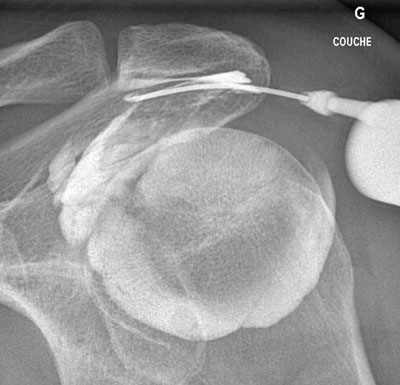

Infiltration de la bourse sous-acromio-deltoïdienne de l'épaule en quatre étapes